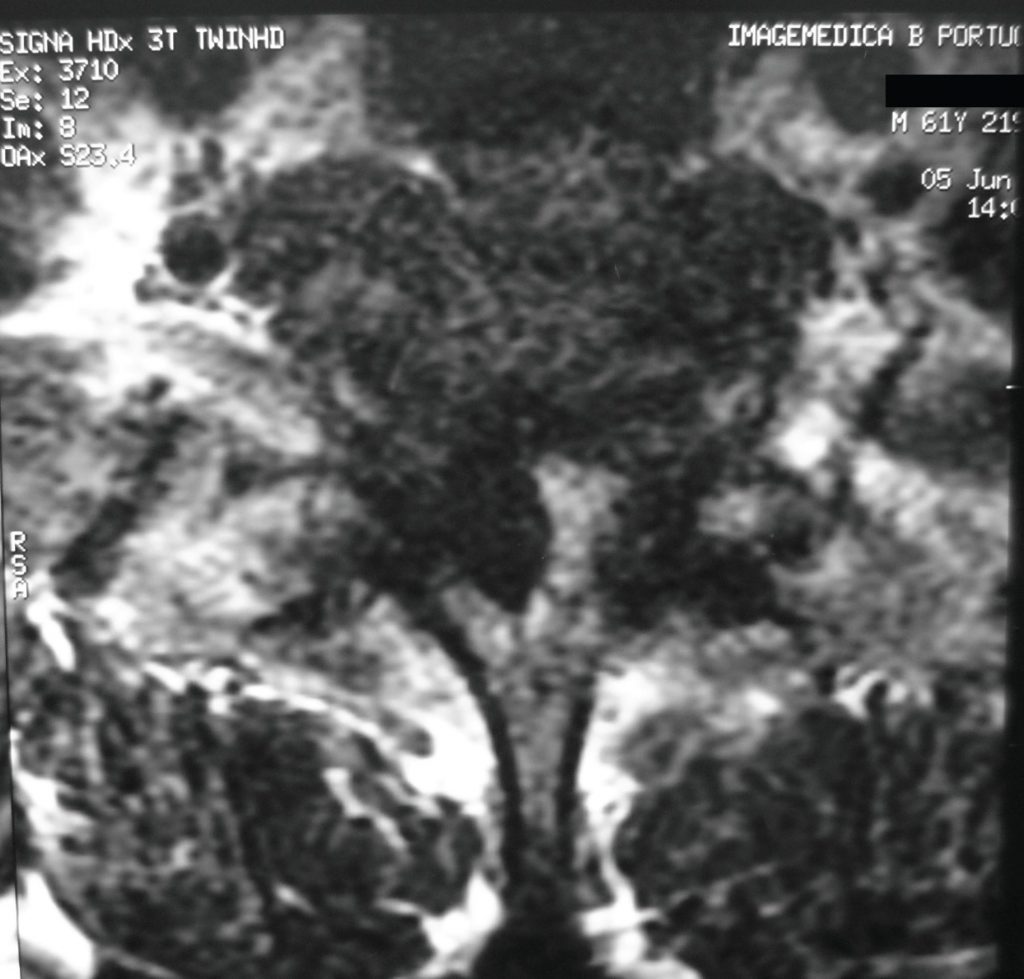

Descrever o mecanismo causador de hematoma epidural com déficit neurológico e revisão da literatura. Relata-se caso de paciente com 62 anos, do sexo masculino, com hematoma epidural pós-traumático da coluna cervicotorácica, com desenvolvimento neurológico progressivo, resultando eventualmente em paralisia completa abaixo de T1. Durante o esvaziamento cirúrgico foi observada compressão significante da coluna vertebral devido ao hematoma em organização. Após cirurgia houve melhora das funções motoras e recuperação completa do déficit neurológico pós-reabilitação. O hematoma epidural pode ocorrer tardiamente a eventos traumáticos, levando a lesões neurológicas de graus variados.